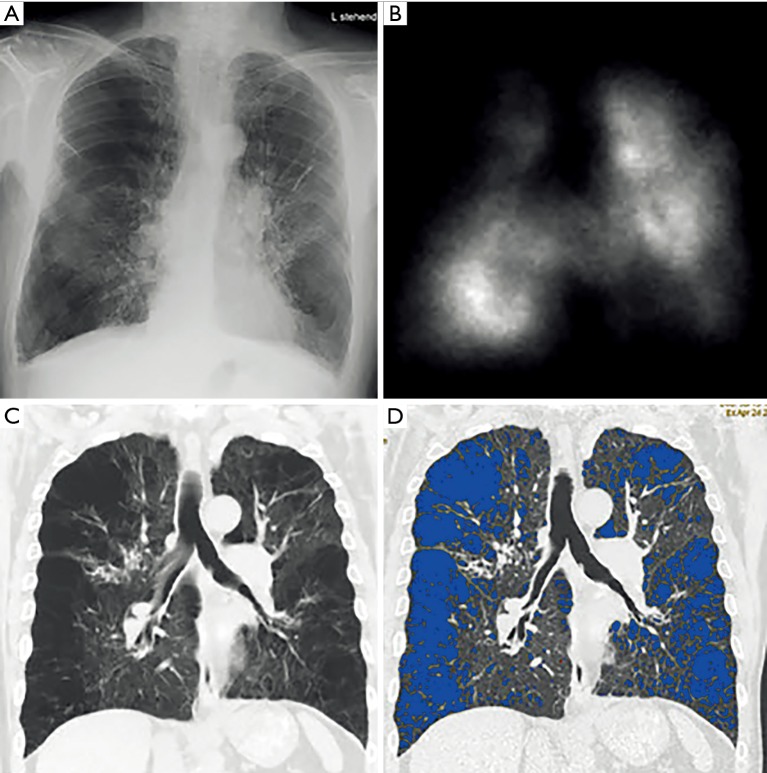

Another technique, which can be employed to evaluate patients with severe emphysema who are candidates for LVR is scintigraphy (Figure 6). Scintigraphy allows for visualizing ventilation and perfusion of the lungs and is therefore able to show upper-lobe predominance and heterogeneity of emphysema. Lung scintigraphy is helpful to identify the most severely affected parts of the lungs in heterogeneous emphysema, but struggles in cases of homogeneous emphysema (43). Quantification is done by dividing the lung in three distinct areas (i.e., upper, middle and lower area) and calculating the percentage of uptake of tracers divided into ventilation and perfusion for each particular zone.

Figure 6.

Example of lung scintigraphy. A 74-year-old male patient with COPD GOLD IV shows perfusion maps in (A) anteroposterior, (B) right oblique and (C) left oblique perfusion maps. Areas with reduced or no tracer uptake correspond to emphysematous areas of the lung. COPD, chronic obstructive pulmonary disease; GOLD, Global Initiative for Chronic Obstructive Lung Disease.

Several authors showed the high accordance between lung perfusion assessed by HRCT and on scintigraphy, questioning the additional information scintigraphy for lung evaluation making the method superfluous in LVR evaluation as mentioned above (7,44).